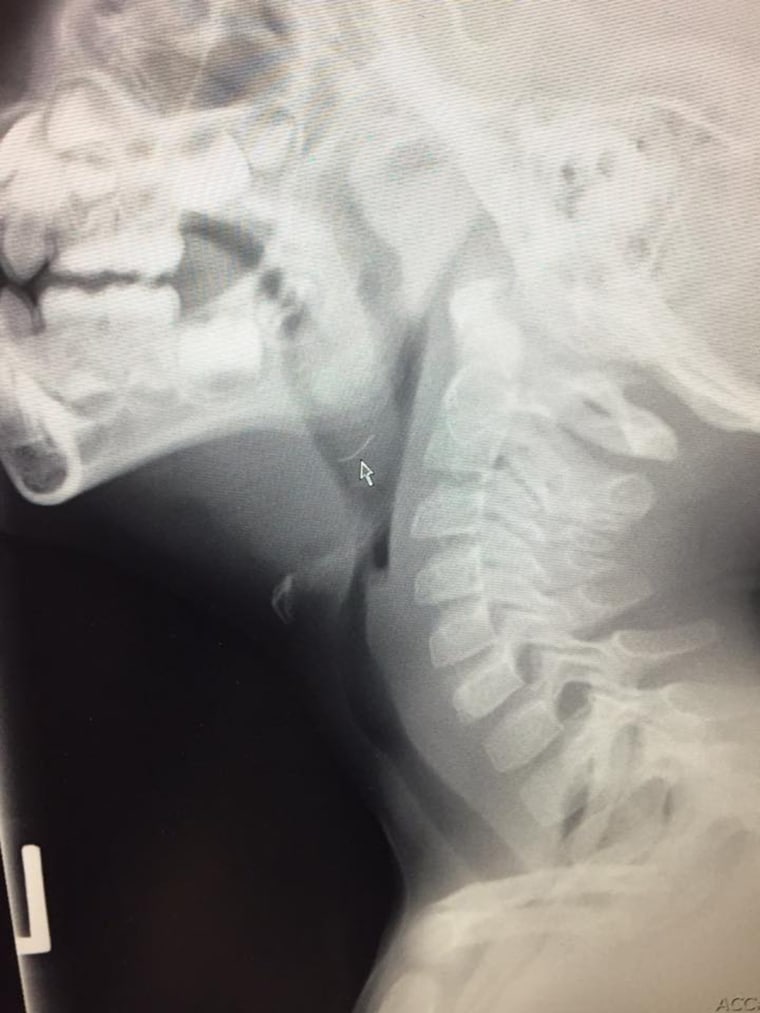

“We did every test we could think of,” says Martin, which included a contrast-enhanced CT scan of the boy's entire neck. Contrast is a substance given orally or intravenously, allowing the organ or tissue being examined to be seen more clearly on a scan, according to Johns Hopkins. The CT scan finally gave the doctors an answer.

“It was a 2-centimeter metal wire that was lodged in the tissue of the tonsils,” Martin says, adding that the wire was so deep that it was not visible during the throat exam.

Later, Martin says doctors learned that the boy's symptoms began while eating at a barbecue. The 2-centimeter metal wire was a bristle from a wire barbecue brush, which broke and ended up on a hamburger.